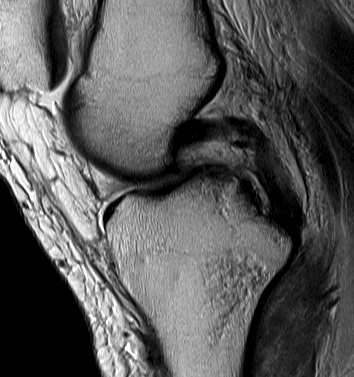

MRI

PCL completely torn

PCL midsubstance tear with lengthening

PCL tibial avulsion

PCL femoral avulsion